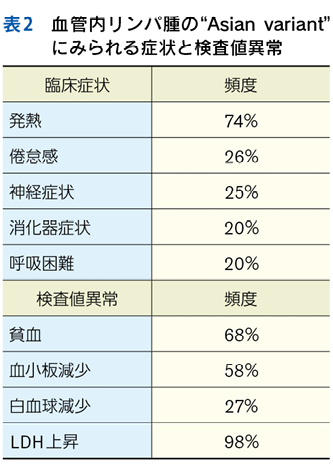

▶ こちらは初期評価不十分のまま多数の介入がなされたケースである。患者が呈している「プロブレム」をまとめて,「皮疹,肝機能異常,腎障害,汎血球減少を伴う遷延性発熱」とフレーミングし,たとえば血管内リンパ腫や血球貪食を伴う成人スティル病などを考えることも可能だが,現在の症状や検査異常(の一部)は抗菌薬をはじめとした介入の副作用として生じているのかもしれない。すべてのプロブレムが一元論で説明されない可能性も考慮したフレーミングも用意するのが謙虚な態度だろう。